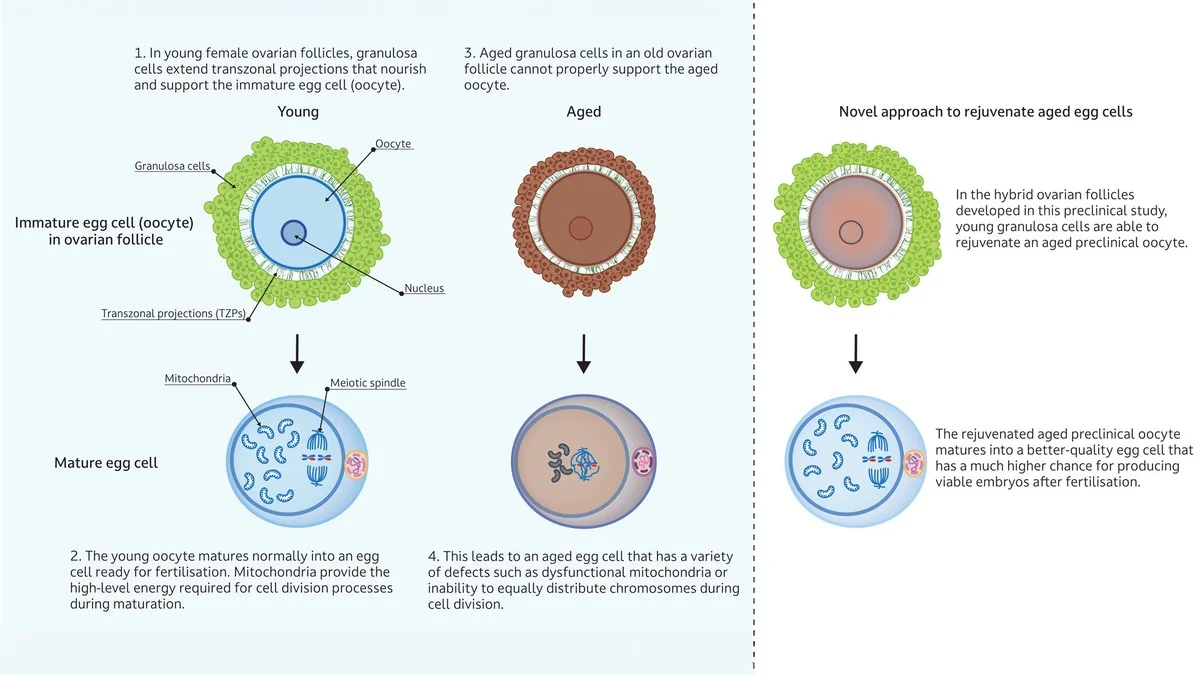

Diese Forschung ist der erste Schritt, um diese Ungleichheit anzugehen. Wenn wir genau verstehen, wo und wann der REC8-Kleber versagt, können wir vielleicht gezielt eingreifen.

Stellen Sie sich vor, Sie könnten in einer Kinderwunschklinik – vielleicht in München oder Hamburg – eine Behandlung bekommen, die diese Eiweißstruktur stabilisiert, bevor überhaupt Probleme auftreten. Das wäre ein technologischer Sprung, der Millionen Frauen neuen Spielraum geben würde.

Die Forscher vermuten, dass der krasse Anstieg der Fehler um die Altersgrenze nicht nur am REC8 liegt, sondern am „kollaborativen Versagen“ mehrerer Teile des Chromosomen-Trennsystems. Aber die Möglichkeit, REC8 isoliert so präzise zu studieren, ist der wichtigste neue Schritt nach vorn.

Bevor diese Erkenntnisse in die breite Anwendung gelangen, ist noch viel Forschung nötig, aber die Richtung ist klar: Wir könnten bald in der Lage sein, die Qualität der Eizellen zu optimieren, bevor die künstliche Befruchtung überhaupt notwendig wird.